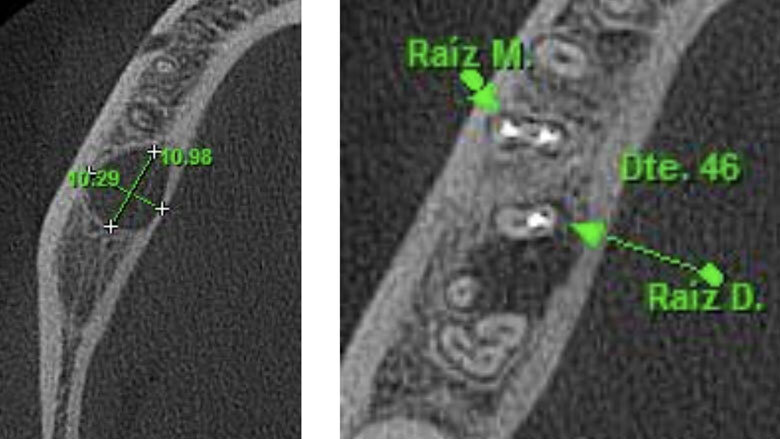

Apicectomía del diente 46.

El reimplante intencional consiste en extraer el diente de manera atraumática, fuera de boca examinar la causa que produce la infección, y volverlo a reimplantar en el menor tiempo posible.

El reimplante intencional consiste en extraer el diente de manera atraumática, y entonces fuera de boca examinar la causa que produce la infección, y volverlo a reimplantar en el menor tiempo posible.

Varios autores han recomendado para la exodoncia evitar el uso de elevadores dentales y limitar la aplicación de los fórceps dentales a la corona del diente como un medio para minimizar el traumatismo en las células PDL. Para algunos, este paso es considerado como la parte más sensible de la técnica del procedimiento5.

Se debe proteger al máximo la integridad de las células del ligamento periodontal, para que se dé una buena cicatrización de las mismas durante la reimplantación. La manera de protegerlas es usar un tiempo extraoral extra corto, no mayor a 15 minutos y entre más bajo mejor. Después de la extracción del diente, las raíces se examinan en busca de fracturas, conductos adicionales o istmo y cualquier característica anatómica adicional que requiera sellarse para evitar la salida de bacterias al exterior. La inspección de la raíz se realiza mejor con la ayuda de un microscopio dental6. Dado que no se necesita una osteotomía, la reimplantación no produce la pérdida de hueso vestibular o palatino para llegar al ápice radicular. Esto facilita la curación postoperatoria al no sacrificar hueso sano para llegar al sitio donde se ubica el ápice radicular. Durante la apicectomía convencional, el campo de visión está limitado por la osteotomía y las estructuras adyacentes, como el arco cigomático y el tejido de la mejilla. Sostener un diente extraído permite un acceso total para inspeccionar toda la superficie de la raíz (4). La manipulación de instrumentos microquirúrgicos y ultrasonidos es más fácil con el diente fuera de la boca. Una reducción del tiempo extra oral es imprescindible en la prevención de la anquilosis, la reabsorción radicular y para promover el proceso de curación peri-radicular mediante la prevención del daño y deshidratación de las células periodontales7. Es grandioso darse cuenta cómo los pacientes quedan altamente agradecidos por conservar sus dientes. Es el endodoncista o el odontólogo el que decide desahuciar dientes que pueden salvarse, y si como especialistas nos entrenamos en técnicas avanzadas, más dientes podremos salvar de la pérdida. En muchos casos, factores económicos impiden que un paciente que pierde los dientes, pueda reemplazarlos, y la falta de dientes está relacionado con problemas gastrointestinales, con cáncer de estomago, cáncer colon rectal e inclusive con Alzheimer8.9. Debemos de verdad aumentar el valor que le damos a los dientes naturales; si fuéramos a perder un riñón, ¿no agotaríamos todos los recursos por salvarlo? Nuestra meta debe ser lograr que nuestros pacientes lleguen con sus dientes naturales hasta la vejez.